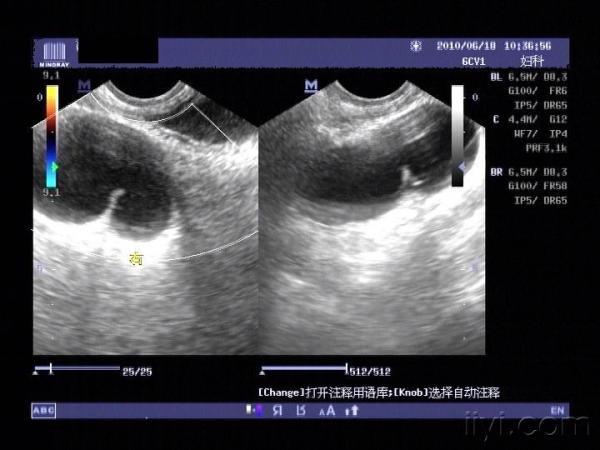

大家来帮我看看,右边这个是输卵管积水还是卵巢囊肿?

右侧附件区和左侧附件区各见一囊性包块

右侧附件区的包块。